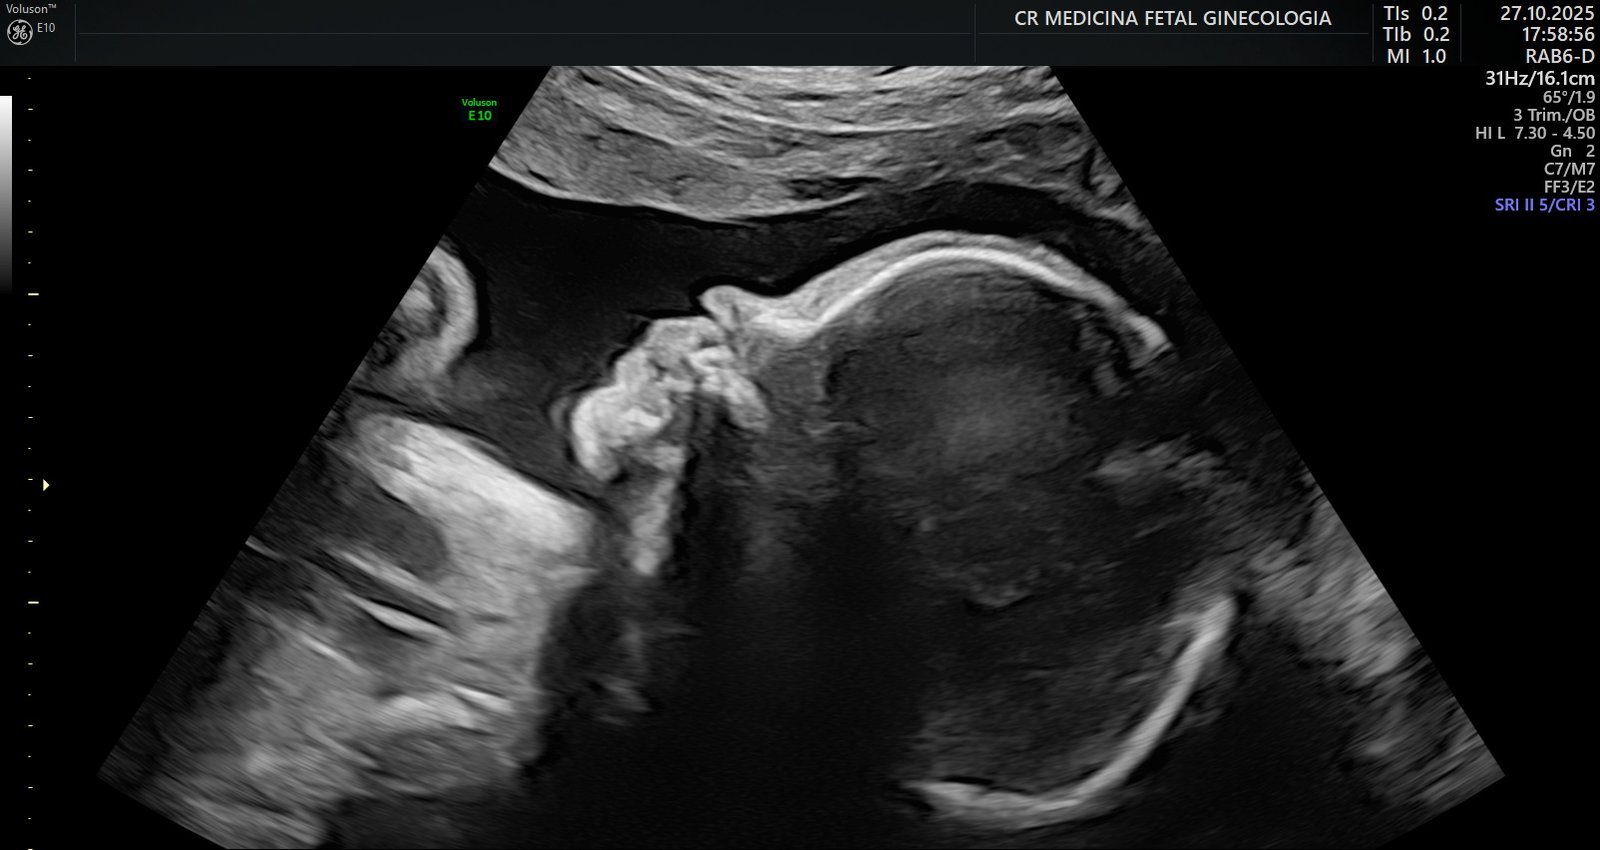

Avaliações de crescimento e ganho de peso fetal no terceiro trimestre: Monitoramento da curva de crescimento, da nutrição e do bem-estar do bebê, garantindo segurança até a reta final da gestação.

Ultrassonografia 3D e 4D: Permite visualizar o bebê em alta definição, em tempo real, em qualquer idade gestacional, proporcionando um vínculo ainda maior entre a família e o bebê.

• Tecnologia avançada em ultrassonografia 2D, 3D e 4D, com aparelho de ultrassonografia de ponta – Voluson E10